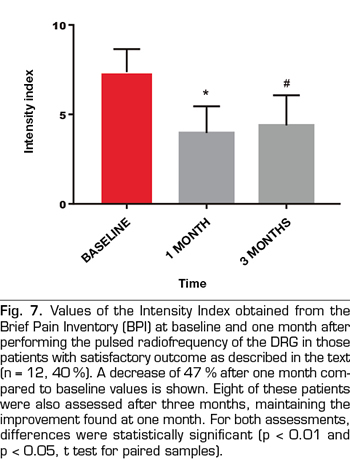

Results: The VNS score decreased from 7.7 ± 2,2 to 5.9 ± 3 (p < 0.01). Intensity and Interference Scores were reduced from 7.1 ± 1.5 to 5.9 ± 2.1 (p < 0.01) and 7.1 ± 1.9 to 6.0 ± 2.3 (p < 0.02) respectively. In 12 patients (40 %) a satisfactory analgesic response was observed. In these patients the VNS decreased from 8.0 ± 1.5 to 3.8 ± 2.6. Intensity and Interference Scores were reduced from 7.4 ± 1.3 to 3.9 ± 1.5 (p < 0.0001) y 7.7 ± 1.9 to 4.9 ± 2,7 (p = 0.002) respectively.

The score in the VNS prior to the procedure was reduced from 7.7 ± 2.2 to 5.9 ± 3 (p <0.01, t test for paired samples), taking into account the entire sample (n = 30), which implies a variation of 23% (Table I, Figure 3). The Intensity Index decreased from 7.1 ± 1.5 to 5.9 ± 2.1 (p <0.01), which implies a change of 16%, while the Interference Index decreased by 15% (7.1 ± 1.9 to 6.0 ± 2.3) (p <0.02) (Table I, Figures 4 and 5). When evaluating the patients who responded favorably using VNS, 12 out of 30 patients showed a decrease of at least 2 points on that scale, representing 40% of the sample. If we analyze these patients separately, we can observe that the initial values of VNS decreased from 8.0 ± 1.5 to 3.8 ± 2.6 after the procedure, which implies a reduction of 53% (Table II, Figure 6).

Ten out of these 12 patients showed a variation of three points or more in VNS (more than 50% variation), whereas only 2 patients had a variation of two points on the scale (30% variation). In this group of patients, the Intensity and Interference Indexes were reduced by 47% and 36%, respectively, from 7.4 ± 1.3 to 3.9 ± 1.5 (p <0.0001) for the Intensity Index and from 7.7 ± 1.9 to 4.9 ± 2.7 (p = 0.002) for the Interference Index (Table II, Figures 7 and 8). The 30 patients included reported an average of subjective improvement of 59%. No complications of the procedures were recorded in these cases.

In eight patients with a satisfactory outcome after one month, a three-month evaluation of the procedures was conducted. In these, the VNS remained at low values, 3.8 ± 3.3 (p = 0.007), something similar happened with the Intensity and Interference Indexes, being 4.3 ± 1.6 and 5.4 ± 2.5, respectively (p = 0.001 and p = 0.02, when compared with the baseline values (Figures 6, 7 and 8).